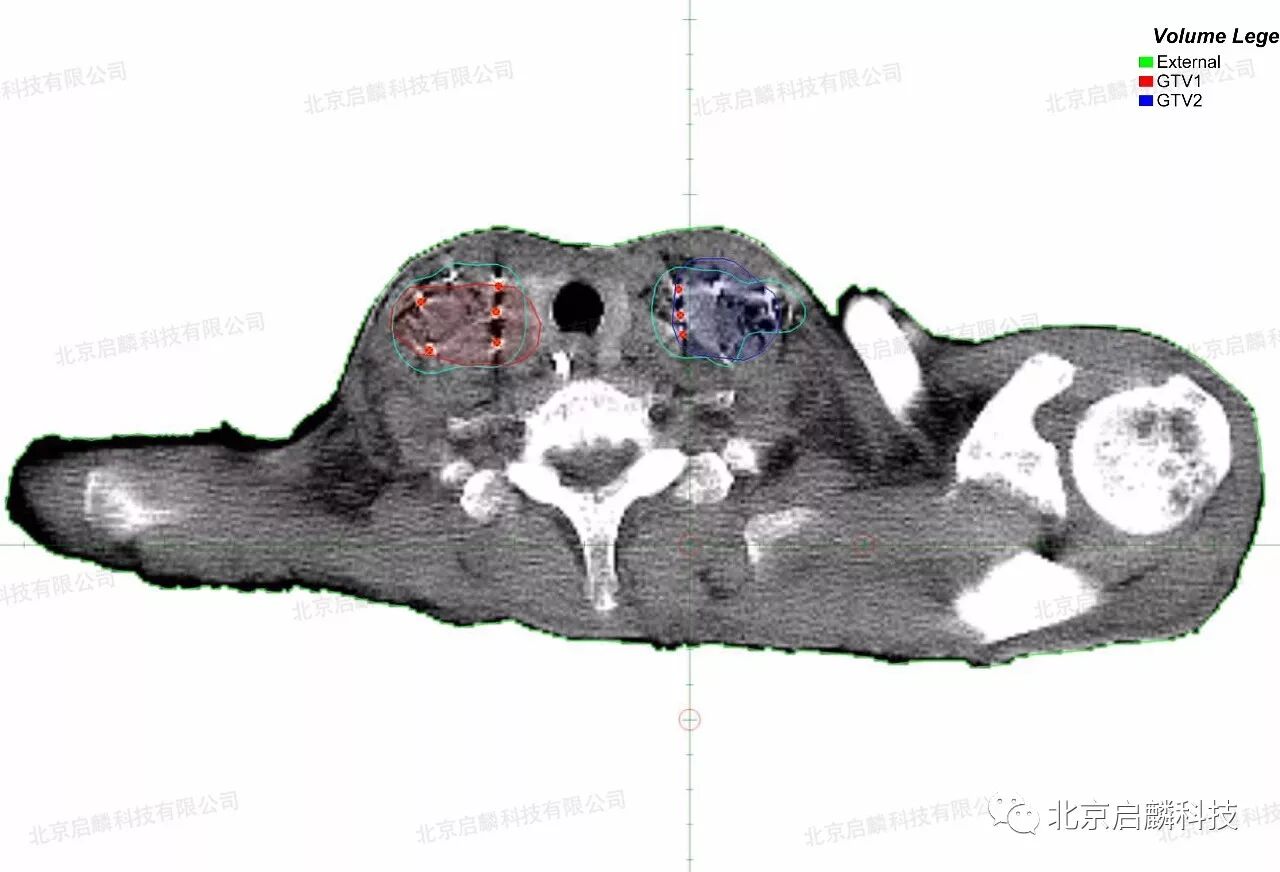

术后对粒子的分布作出剂量分析,完全符合术前的组织计划剂量,做到了更加便捷、精准、微创,使瘤体局部放射学剂量最优化。

术后粒子植入分布

术前、术后对比DVH放射剂量分布均匀